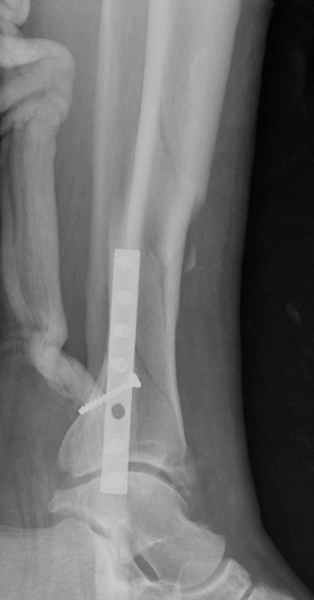

Здесь мы использовали новый Synthes Nail с дополнительными дырками, в проксимальной части 4: по две косых и поперечные (один стандартный а другой динамический), в дистальной части две поперечные, прямая и косая. Вес больного более 120 кг, нагрузку начнем через месяц.

Получилось красиво, поздравляю. Вверху можно было ограничиться одним винтом во фронтальное статическое отверстие, зачем два 45-градусных?

При такий спирали задний край tibia может быть сломан - нет ли этого в данном случае? На всякий случай можно было ввести 1-2 винта 4,5 мм спереди назад мимо гвоздя. Хотя самый дистальный блокирующий винт, возможно, зацепил этот отломок. А какой тут диаметр гвоздя и locking винтов?